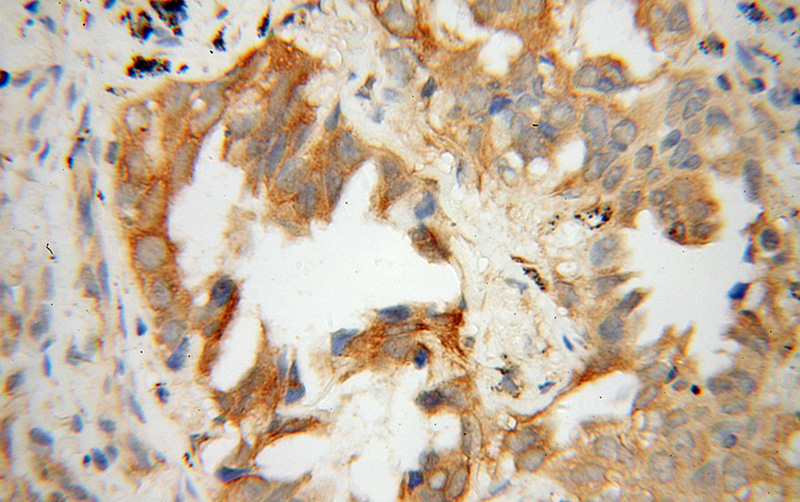

Immunohistochemical of paraffin-embedded human lung cancer using Catalog No:112529(MFN1 antibody) at dilution of 1:100 (under 40x lens)